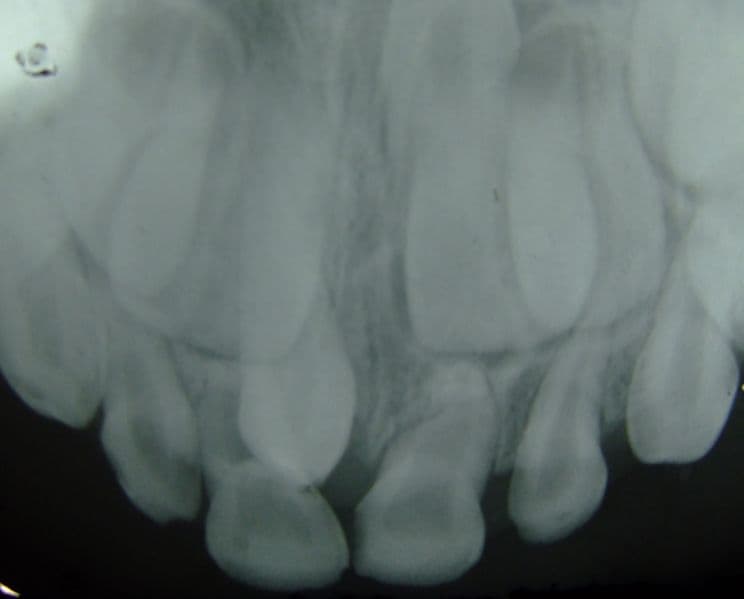

Dentro de los rasgos físicos característicos del talentoso músico británico, destacó siempre la prominente dentadura que se asomaba cada vez que cantaba. Esta característica en realidad fue una condición diagnosticada: hiperdoncia.

Esta condición se refiere a poseer más dientes de lo habitual. No es un fenómeno muy común, pero suele presentar los primeros signos en la niñez: cualquier persona que desarrolle más de 20 dientes de leche podría padecer hiperodoncia, aunque eso sólo podría confirmarse al momento de que los dientes permanentes comienzan a salir.

A los dientes extra se les conoce como supernumerarios, y de acuerdo a la Asociación Dental Canadiense (CDA, por sus siglas en inglés), el 85 % de ellos aparecen en el maxilar superior.

De acuerdo con Peter Freestone —asistente personal de Freddie y autor del libro Freddie Mercury: An Intimate Memoir by the Man who Knew Him Best— el cantante fue diagnosticado con hiperodoncia desde antes de saltar a la fama: tenía para ser exactos cuatro dientes adicionales en la mandíbula superior que empujaban sus dientes frontales.